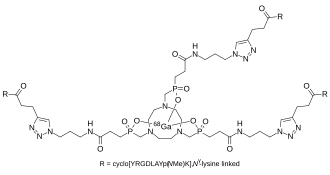

Like most precursors used for radiolabeling with radioactive metal cations, Trivehexin is composed of a dedicated complex ligand (a so-called chelator) for kinetically inert binding of the 68GaIII ion, and the bioligand(s) for binding to αvβ6-integrin. The chelator comprised in Trivehexin is a triazacycloalkane with 3 phosphinic acid substituents, with the basic structure 1,4,7-triazacyclononane-1,4,7-triphosphinate[16] (frequently abbreviated TRAP).[17][18][19] The αvβ6-integrin binding molecular unit is a cyclic nonapeptide with the amino acid sequence cyclo(YRGDLAYp(NMe)K).[1]

In the Trivehexin molecule, three of these cyclopeptides are attached by covalent bonds to a single TRAP chelator core. Since TRAP possesses three equivalent carboxylic acids for conjugation of other molecular units via amide formation, Trivehexin is a C3-symmetrical molecule with its three peptide bioligands being fully equivalent. The peptides are attached to the chelator core via the terminal amine group of the side chains of N-methyl lysine. Actually, the conjugation is not done by amide bonding directly, but involves prior functionalization of the peptide with a short molecular extension (a linker) bearing a terminal alkyne, and of TRAP with three linkers bearing terminal azides.[19] These components are assembled by means of copper(I) catalyzed alkyne-azide cycloaddition (CuAAC, also known as Huisgen reaction, a Click chemistry reaction), giving rise to the three 1,3-triazole linkages in the 68Ga-Trivehexin structure.[1]